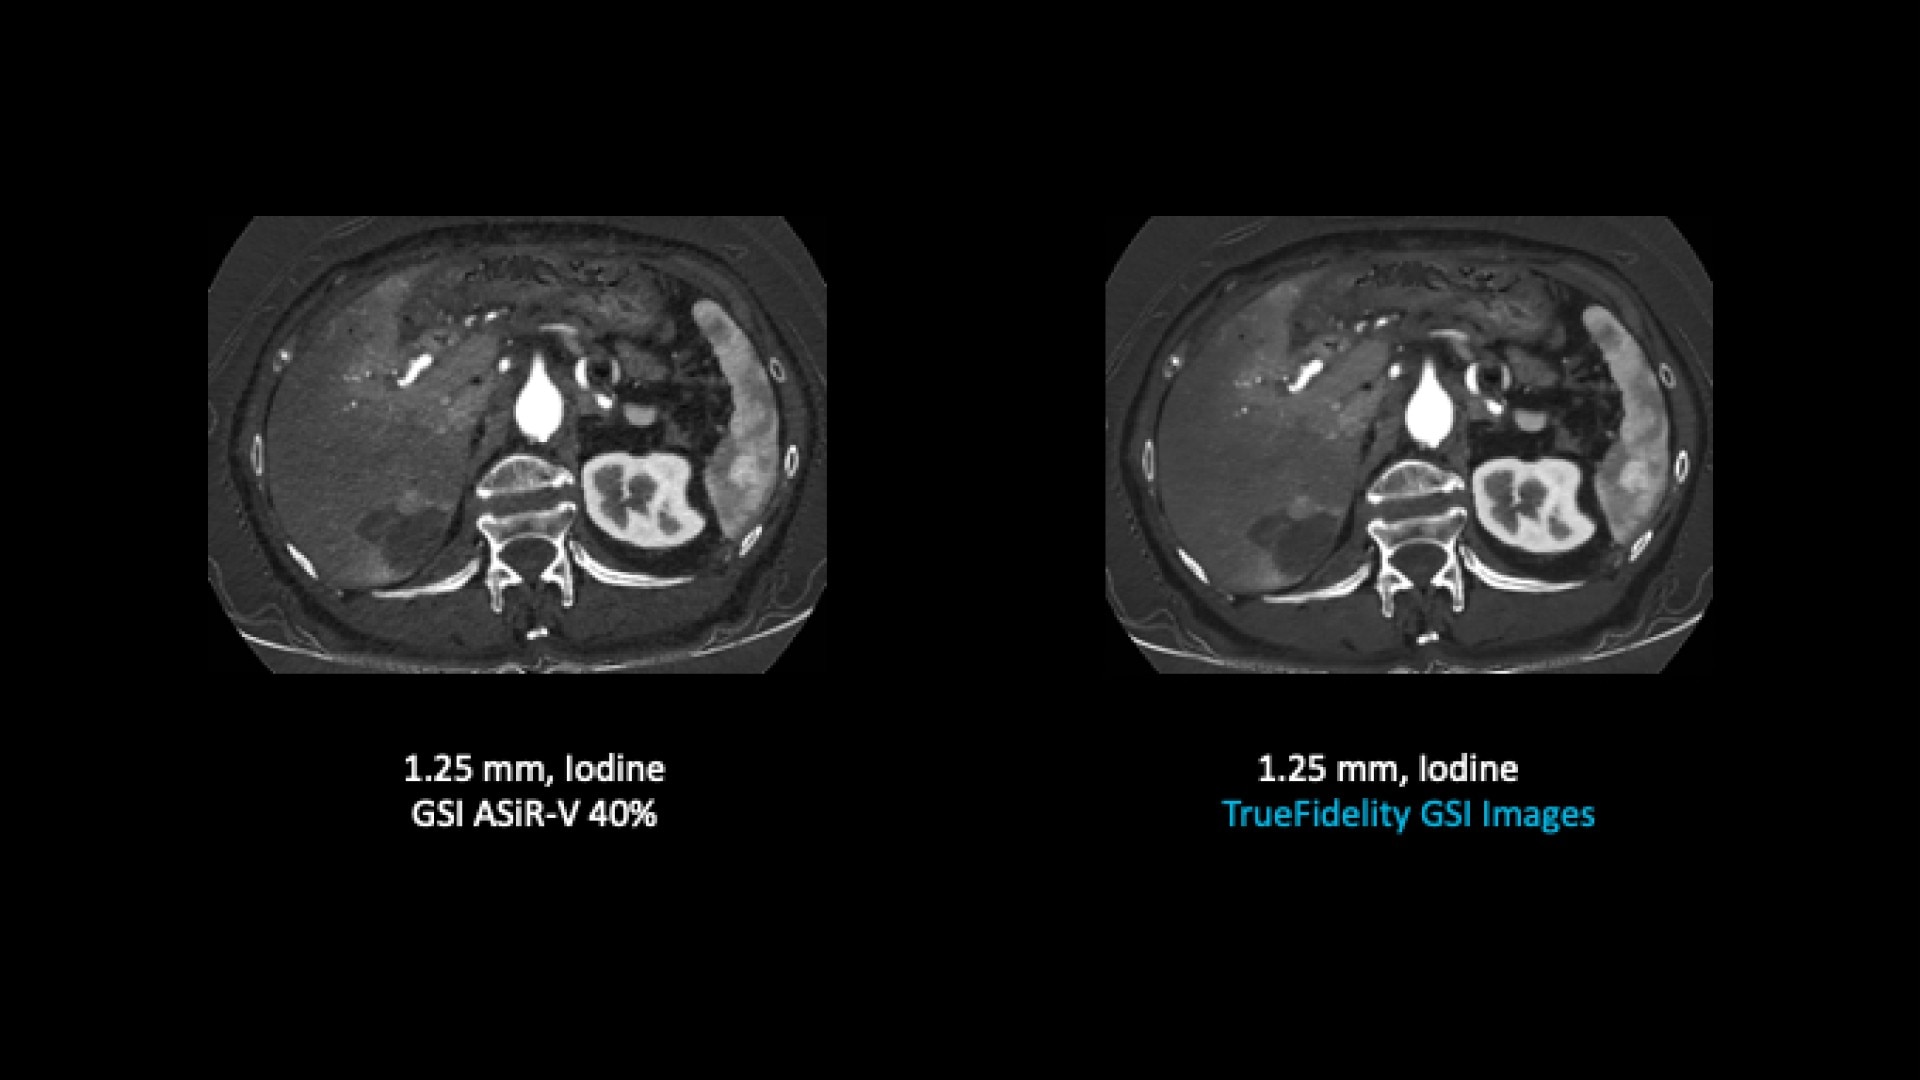

TrueFidelity for GSI now brings the potential to substantially reduce the image noise in all spectral image types

From virtual monochromatic images to material image pairs and virtual non-contrast images, with and without metal artifact reduction. Specifically, reducing the image noise inherent with low keV images resolves one of the traditional technical challenges in adopting more dual-energy protocols across the full patient population.